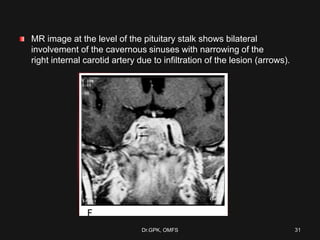

MR image at the level of the pituitary stalk shows bilateral

involvement of the cavernous sinuses with narrowing of the

right internal carotid artery due to infiltration of the lesion (arrows).

Dr.GPK, OMFS 31

MR image atthe level of the pituitary stalk shows bilateral involvement of the cavernous sinuses with narrowing of the right internal carotid artery due to infiltration of the lesion (arrows). Dr.GPK, OMFS 31